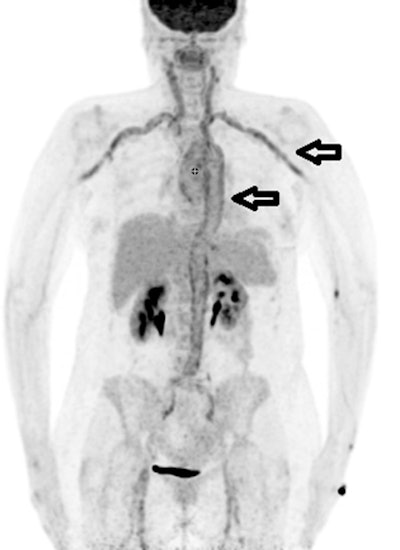

A 68-year-old woman who met the FUO criteria. F-18 FDG-PET/CT torso imaging shows longitudinal uptake along the aorta and the large vessels, pathognomonic for giant cell arteritis (arrows). The patient showed only minimal clinical symptoms for vasculitis. Causal anti-inflammatory therapy with oral cortisone was started, to which patient responded well. Image courtesy of Scientific Reports.The largest part of final diagnoses was assorted to infectious diseases (109/300 patients, 36.3%) followed by autoimmune/rheumatic diseases (51/300 patients, 17%) and malignancy (33/300 patients, 11%), according to the findings.